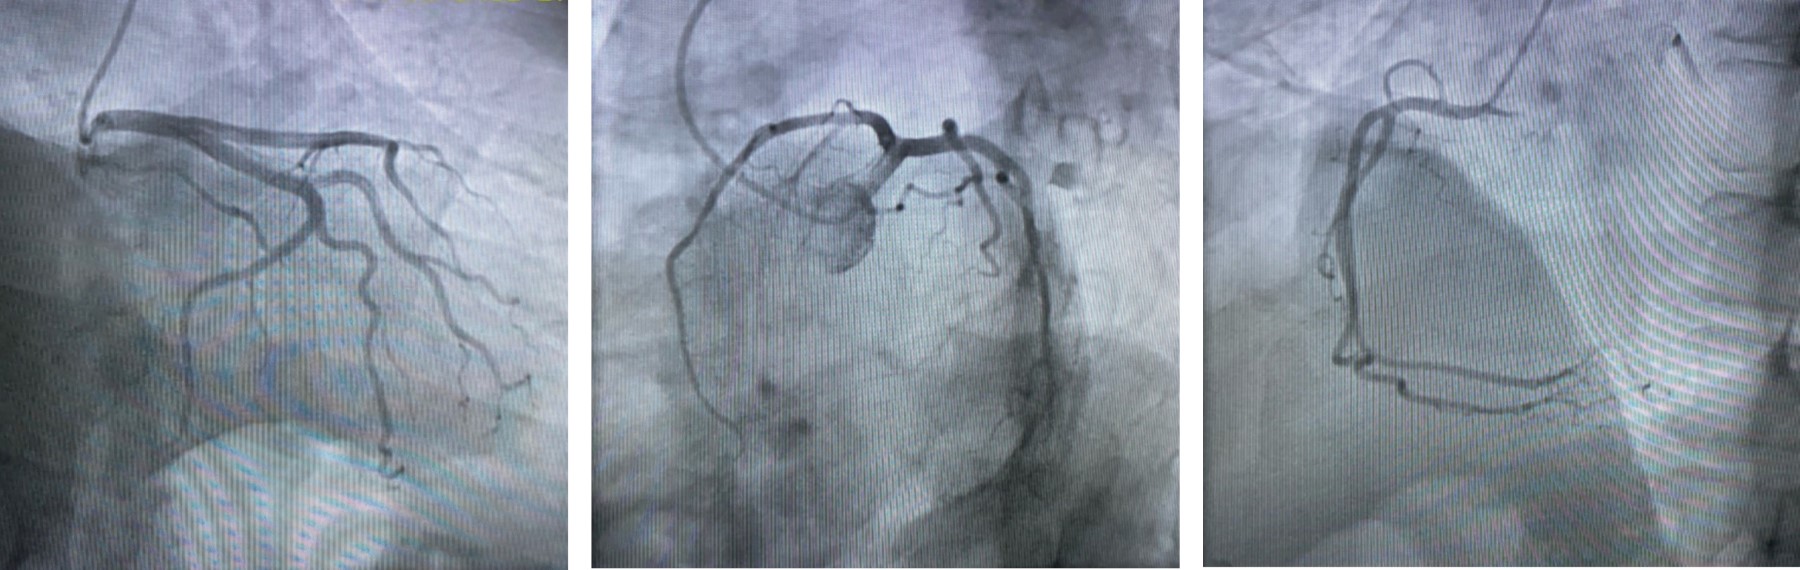

Se presenta el caso de una mujer de 50 años atendida en el Servicio de Urgencias por dolor torácico y elevación de enzimas cardiacas; no tuvo alteraciones electrocardiográficas. Se realizó coronariografía en la que no se encontraron lesiones obstructivas. Un estudio de resonancia magnética cardiaca reportó imagen compatible con miocarditis aguda sin evidencia de isquemia miocárdica. La paciente había recibido una primera dosis de vacuna Pfizer-BioNTech dos días antes de la aparición de los síntomas. En la mayoría de los casos de miocarditis, el diagnóstico etiológico se encuentra indeterminado y sus manifestaciones clínicas tienen un amplio espectro. En los últimos meses, se ha establecido la asociación probable entre casos de miocarditis con vacunas COVID-19 mRNA. El uso de vacunas COVID-19 mRNA ha demostrado el beneficio significativo en la reducción de morbilidad y mortalidad relacionadas a la infección por el virus SARS-COV-2. Este puede ser un proceso transitorio que no representa una contraindicación para la aplicación de la vacuna.

Figura 1